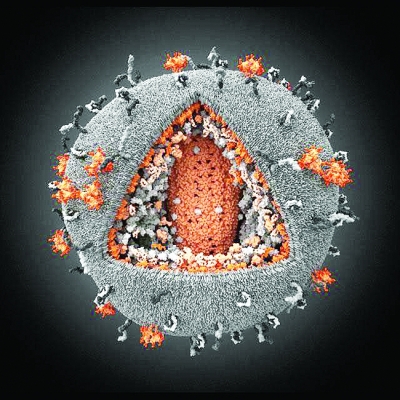

艾滋病病毒的3D模型

或许你会以为这是一个毛线团,事实上这是由位于莫斯科的视觉科学公司的科学家们花费数月创建的艾滋病病毒的3D模型。伊凡·康斯坦蒂诺夫和他的团队用两种颜色描绘了病毒侵入细胞的情景:灰色––免疫细胞;橙色––艾滋病毒。